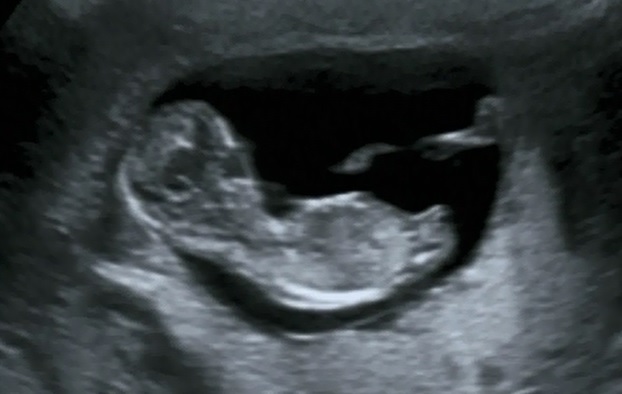

The Echo is taken by 11+6 weeks, im today 12 weeks.